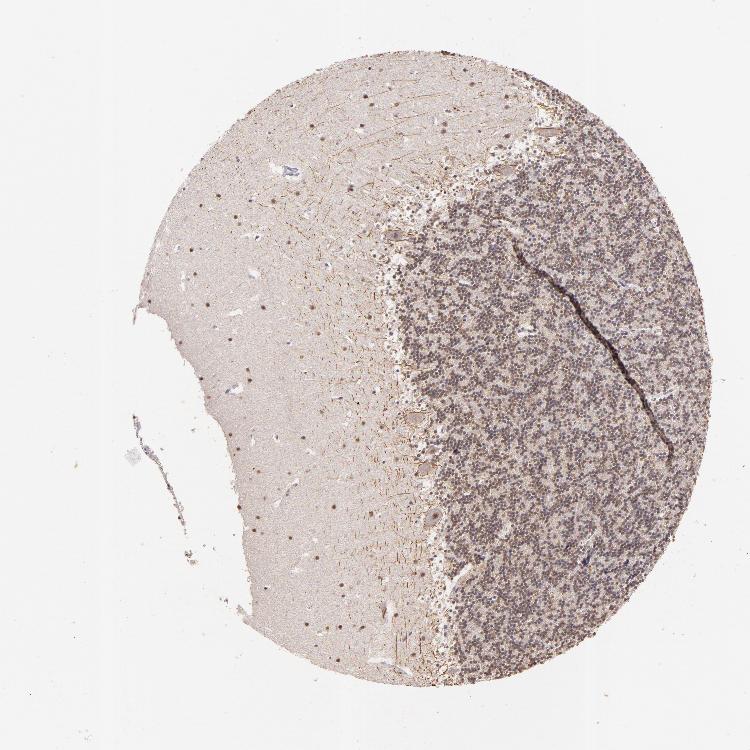

CEREBELLUM - Antibody stainingi

Antibody staining in the annotated cell types in the current human tissue is reported as not detected, low, medium, or high, based on conventional immunohistochemistry profiling in selected tissues. This score is based on the combination of the staining intensity and fraction of stained cells.

Each image is clickable and will lead to virtual microscopy that enables deeper exploration of all samples and also displays staining intensity scores, fraction scores and subcellular localization as well as patient and tissue information for each sample.

Antibody HPA004902Antibody CAB001973

Purkinje cells Not detectedNot detected

Cells in granular layer MediumLow

Cells in molecular layer HighMedium